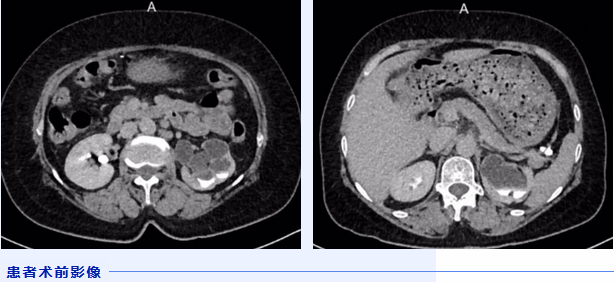

一个月前李阿姨因腰背部胀痛明显,到医院进行详细检查,本以为只是单纯的腰背痛,然而检查结果却给了李阿姨重重一击。医生告诉她,她的左肾有重度积水,肾功能严重受损,如果不尽快切除,会对身体产生严重影响。突如其来的噩耗令李阿姨难以接受,辗转多家医院,得到的都是如出一辙的答案。一天,李阿姨在与邻居黄阿姨的交谈中得知,黄阿姨一个月前在北京积水潭医院贵州医院外科做了双肾结石手术,主治医生是北京积水潭医院泌尿外科专家翟建坡,于是建议她前往就诊,或许能够保住肾脏。

住院完善检查后,翟建坡主任团队为李阿姨实施了第一次手术——左肾造瘘术。这次手术的目的是尽早解除肾梗阻,恢复肾功能。术中,翟建坡主任将肾造瘘管置入李阿姨积水的肾脏内,将积水排出体外,以缓解左肾积水症状。术后,肾造瘘引流情况良好。由于肾功能恢复需要时间,李阿姨要等3个月后再来复查,以确定肾脏有无保留价值。

3个月后,李阿姨接受肾盂和输尿管造影检查,但检查结果并不理想,显示其左侧输尿管完全闭锁,这对于医生来说非常棘手,无疑为手术带来了不小挑战。术前,医生团队进行了详细讨论,第二次手术不仅要在双镜联合下完成左侧输尿管闭锁段扩张术,还要准备腹腔下左肾切除术,如果探查情况不佳,还是要切除左肾。此时,李阿姨的心情再次掀起波澜,她不想自己坚持3个月就此放弃,“我愿意相信你们过硬的医术,只要有一丝希望,哪怕很渺茫,也要试一试!”